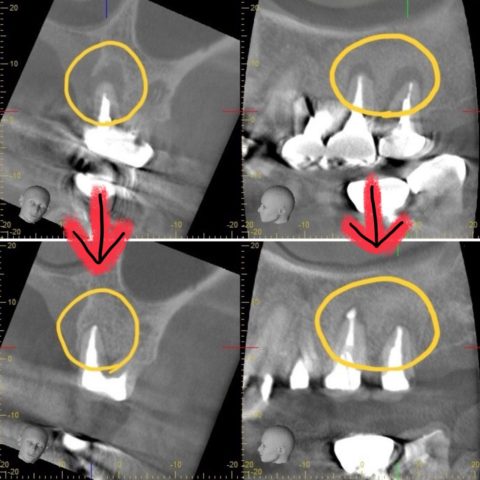

↑CT画像では治療前の根尖病変の透過像が無くなっている事が分かります。